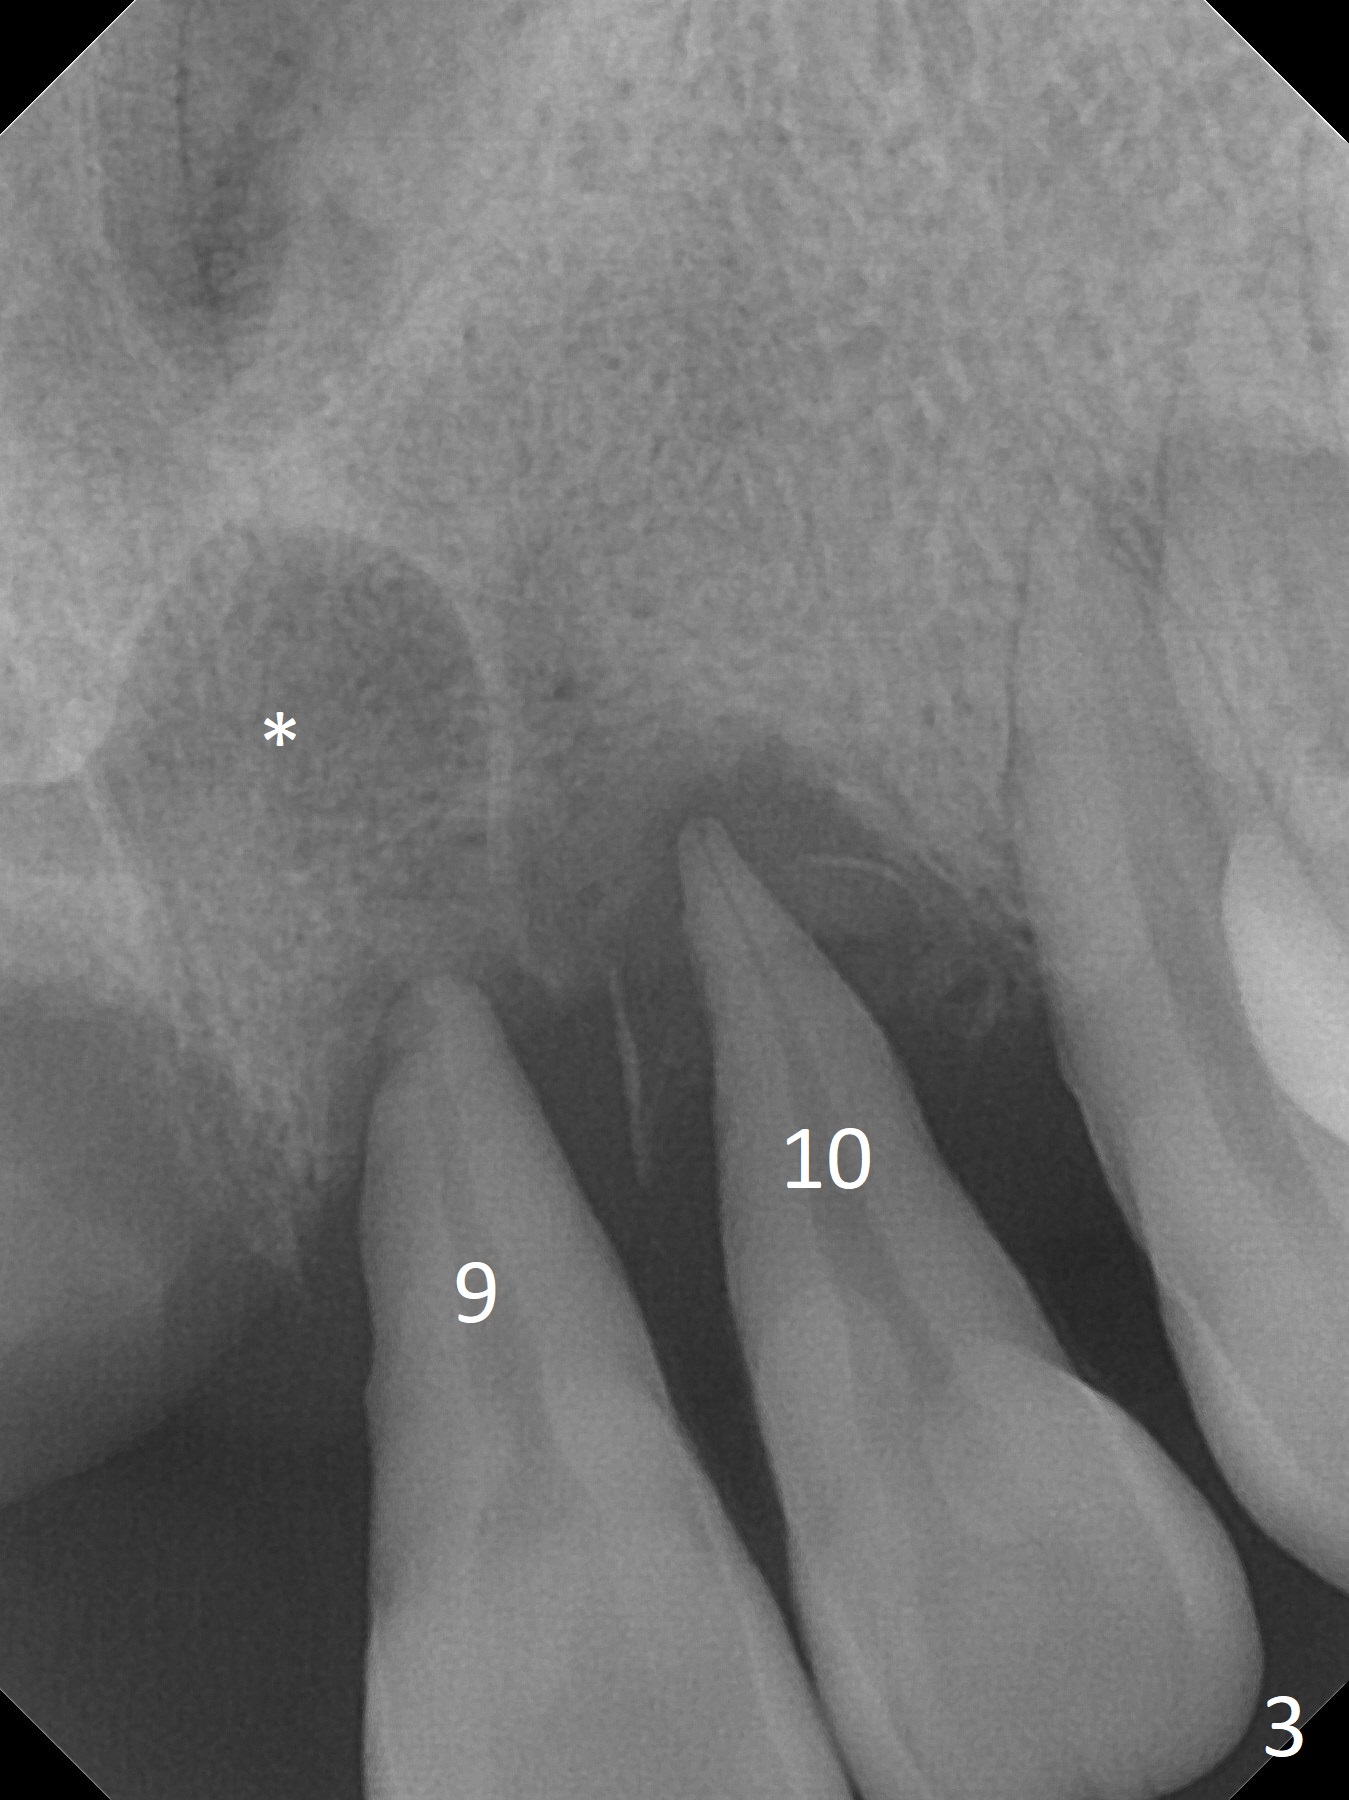

A 41-year-old woman returns to clinic with missing upper right incisors and mobile left ones (#9 fistula (Fig.1 *) 2 years post cementation of 23-25 implant FPD (Fig.2-3). The Incisive Canal is large (Fig.2,3 *). Place all of the 4 implants distally (2.5 or 3x10 or 12 mm (at 8,9), x12 or 14 mm (7,10)) and as deep as possible. The cuff is most likely 4 mm.